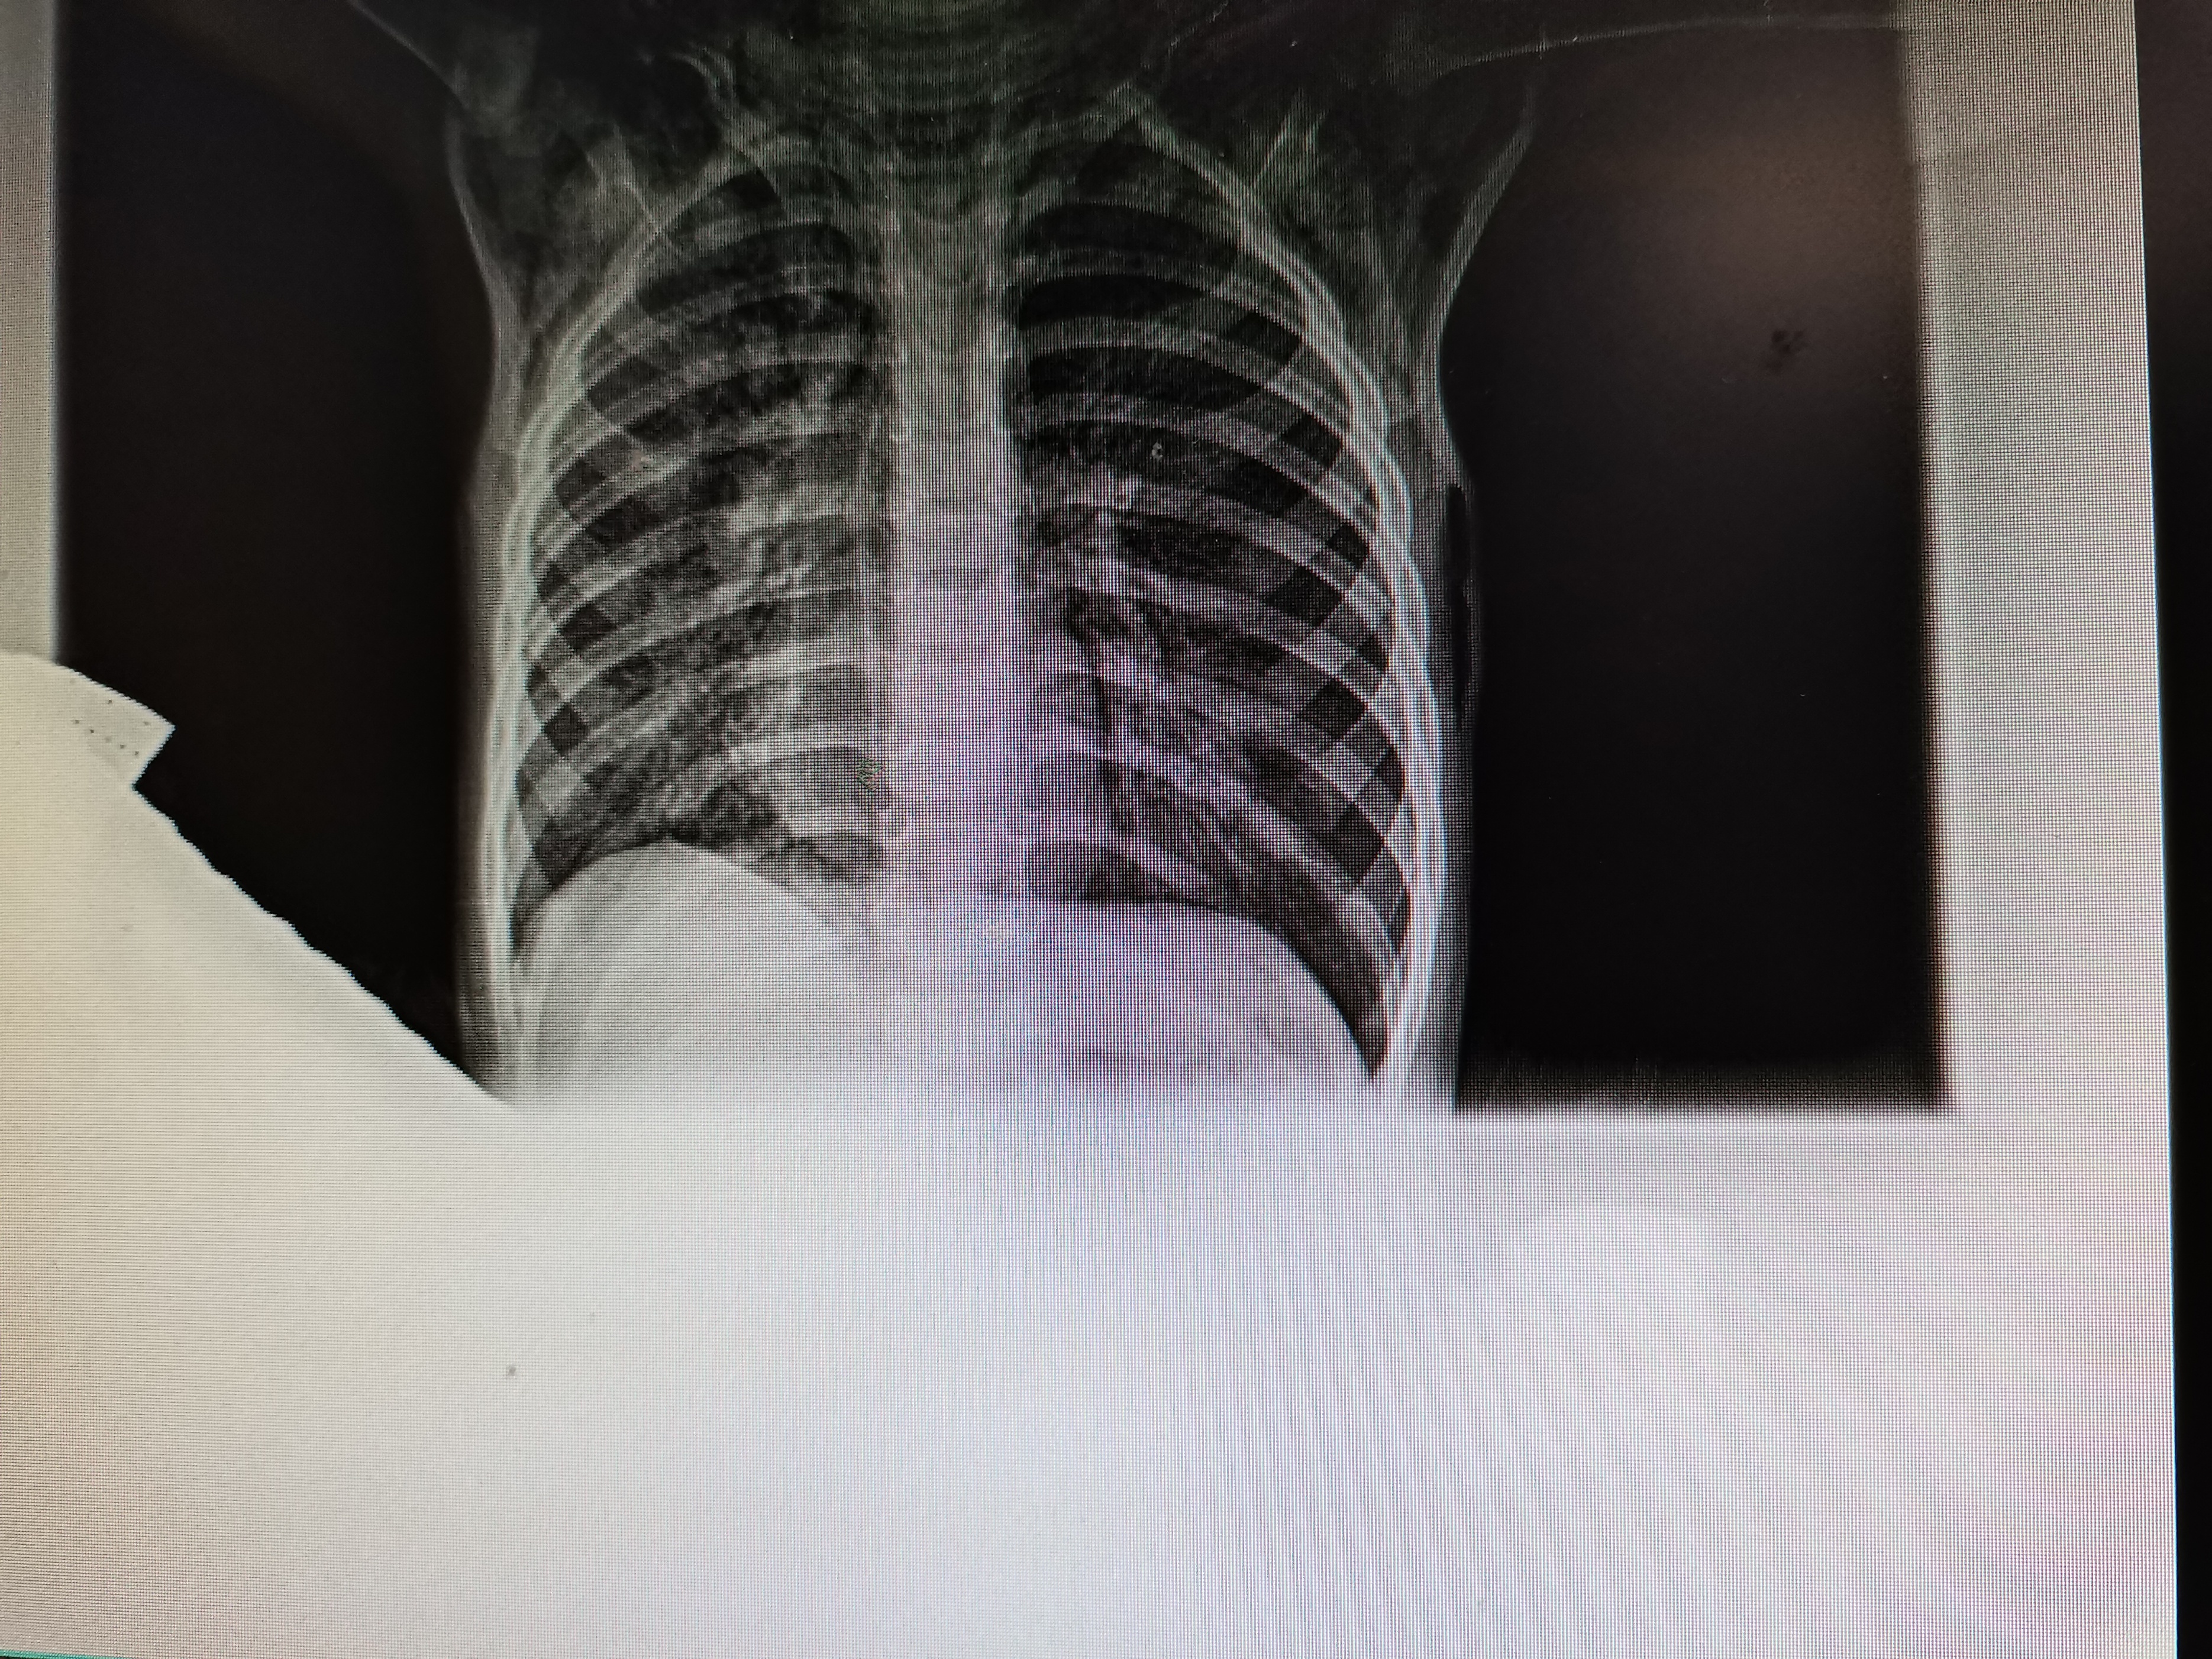

双肺听诊呼吸音不对称,左肺呼吸音明显减低,入院前急诊胸片提示纵隔及皮下气肿,心影偏移。

入住PICU后完善肺部三维重建发现:纵隔、胸壁软组织及颈部软组织皮下积气,纵隔向右侧移位,左主支气管片状高密度影,左肺上叶舌段部分支气管轻度扩张,右肺体积缩小。